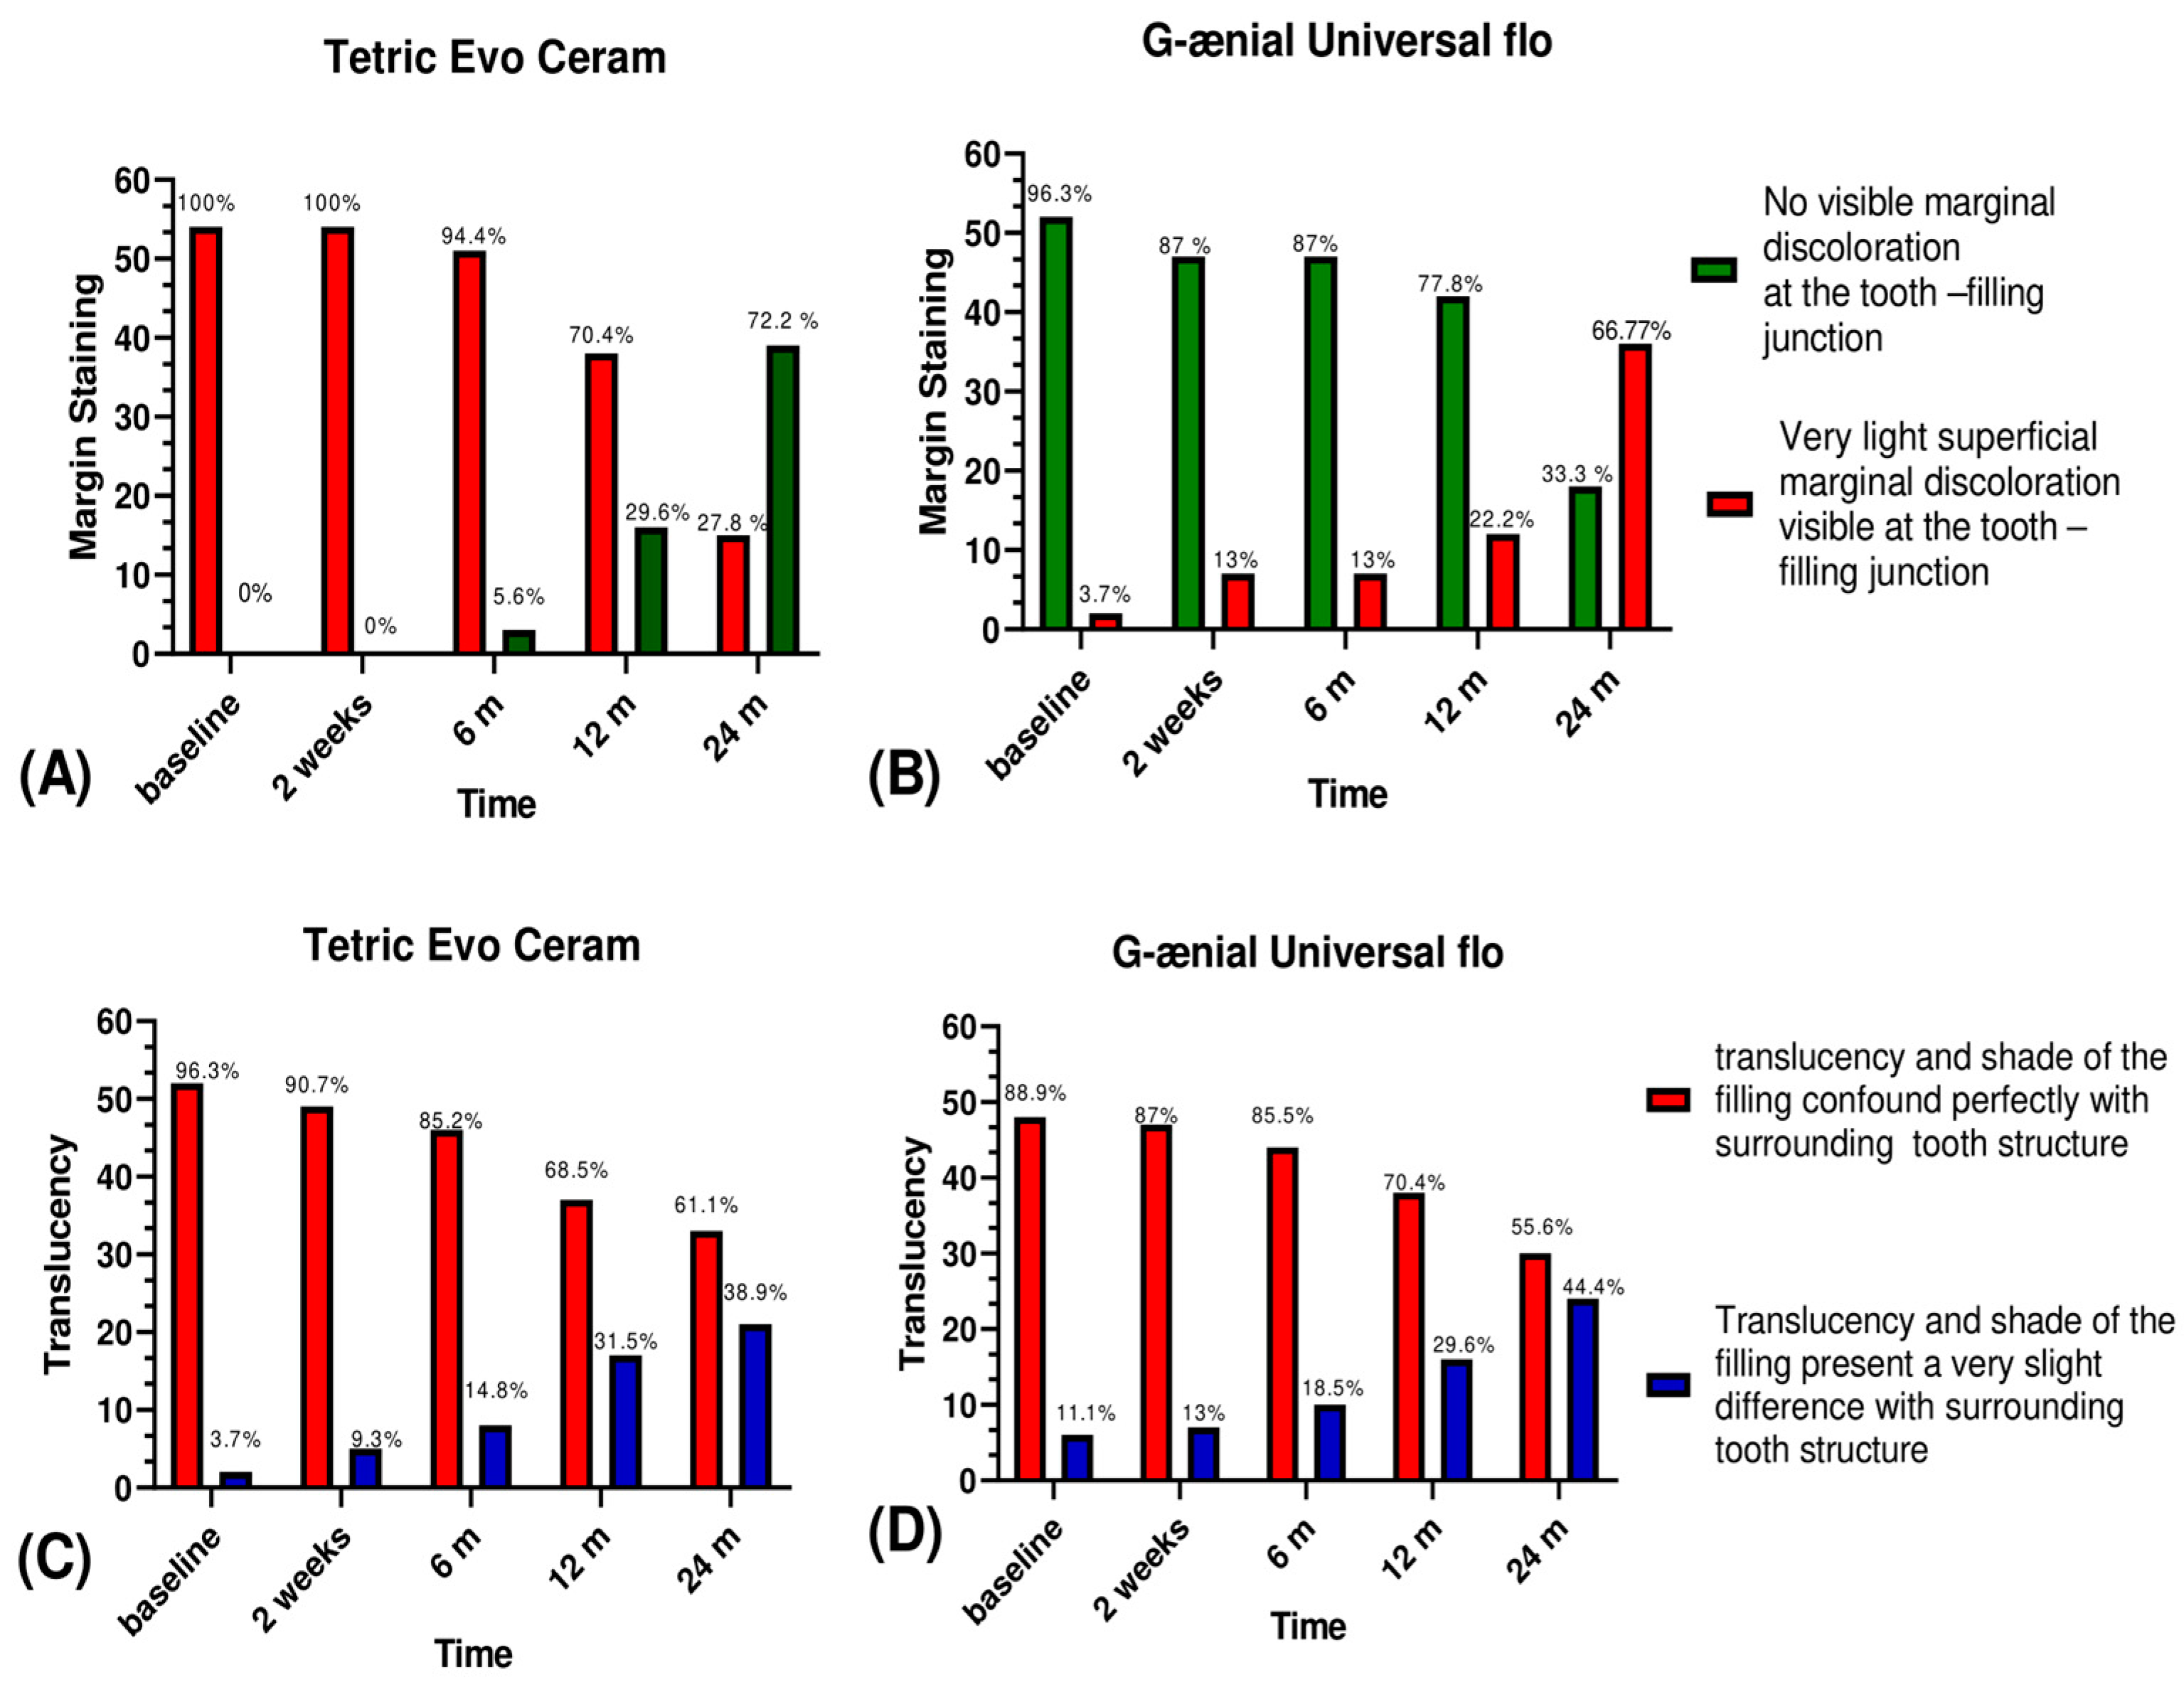

3.1. Esthetic Criteria

3.2. Biological Criteria

| Staining | Surface | No visible staining or discolouration at the surface of the tooth | Very light superficial discolouration or staining is visible at the tooth surface | Visible staining and discolouration at the tooth surface could be removed by polishing | Visible staining and discolouration at the tooth surface with deep penetration that could not be removed by polishing | Very deep surface discolouration | |

| Margin | No visible marginal discolouration at the tooth-filling junction | Very light superficial marginal discolouration is visible at the tooth-filling junction | Visible marginal discolouration at the tooth-filling junction that could be removed by polishing | Visible marginal discolouration at the tooth-filling junction with deep penetration that could not be removed by polishing | Very deep marginal discolouration | ||

| Colour match and translucency | The translucency and shade of the filling confound perfectly with the surrounding tooth structure | The translucency and shade of the filling present a very slight difference with the surrounding tooth structure | The translucency and shade of the filling do not confound perfectly with the surrounding tooth structure but the difference remains acceptable | The translucency and shade of the filling do not confound perfectly with the surrounding tooth structure. The difference is important | The shade difference is severe | ||